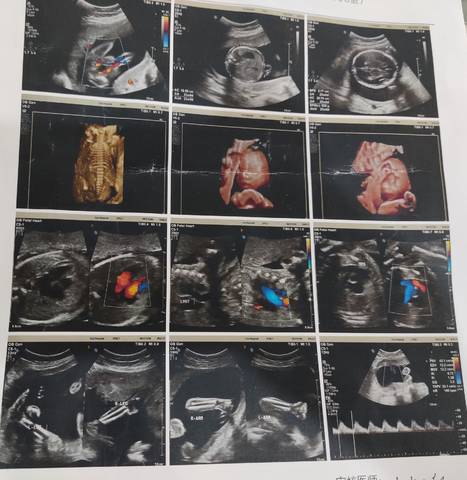

大家帮我看下是男是女?谢谢

你好根据B超单子是看不出男女的只要宝宝健康才是我们最大的心愿不是吗?最后祝宝妈心想事成哦。

你好。我们是判断不了男宝宝跟女宝宝的,孕期定期检查,我觉得宝宝健康就好的。祝心想事成 。

亲爱的,通过这些判断不出来是什么样性别的哈,反正宝宝发育好就是最好的哈,祝你好孕。

亲,我们都是一样觉得好奇,确实没什么依据,不要想太多,生下来最准确的,一切顺利!